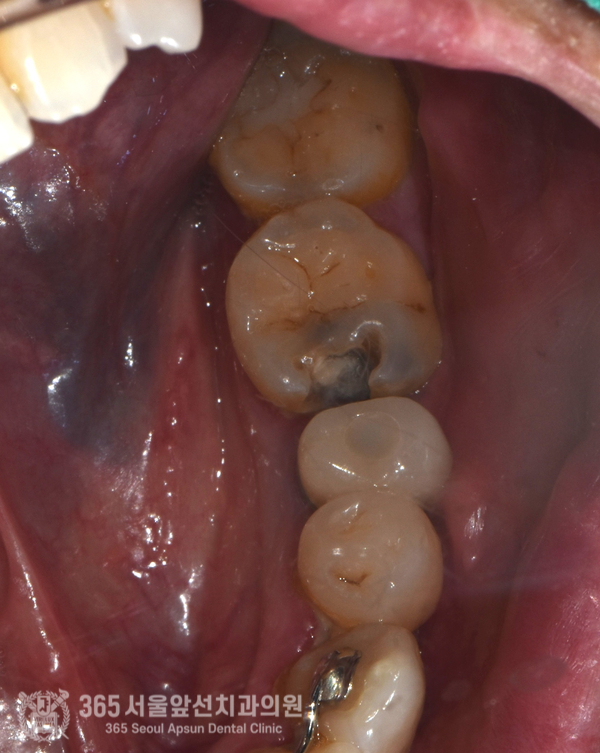

촬영일시 : 2024.06.01 초진 내원당시 사진입니다. 큰 어금니의 앞쪽에 까맣게 충치(치아우식증)가 진행되어 구멍이 크게 뚫린것이 관찰됩니다.